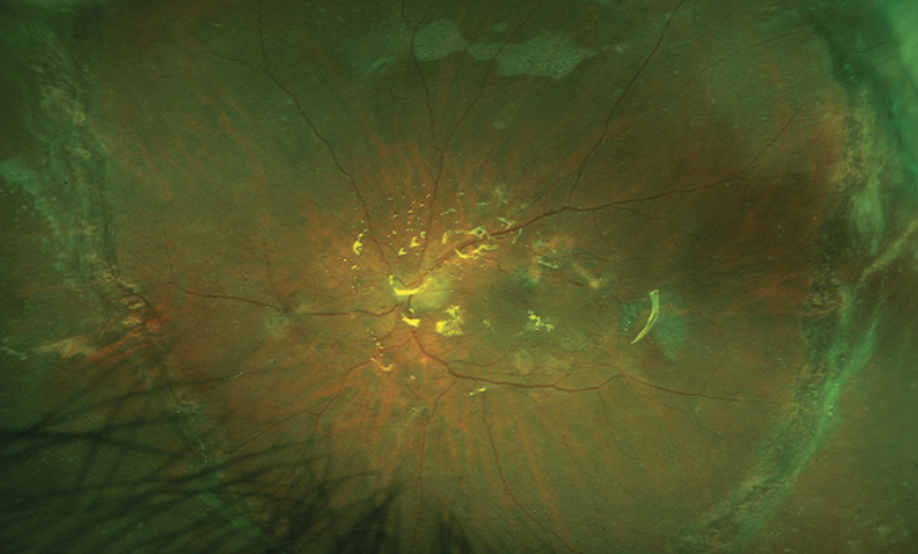

The patient has been followed for 4 months, and the retina has remained attached with a BCVA of 20/400 and IOP of 12 mm Hg (Figure 2). No reproliferation of membranes has occurred, and silicone oil has not migrated into the anterior chamber. Silicone oil removal is anticipated in the coming months.

<p>Figure 2. Widefield color photograph shows the retina attached under silicone oil with laser scars on the edges of the giant retinal tear.</p>

Figure 2. Widefield color photograph shows the retina attached under silicone oil with laser scars on the edges of the giant retinal tear.